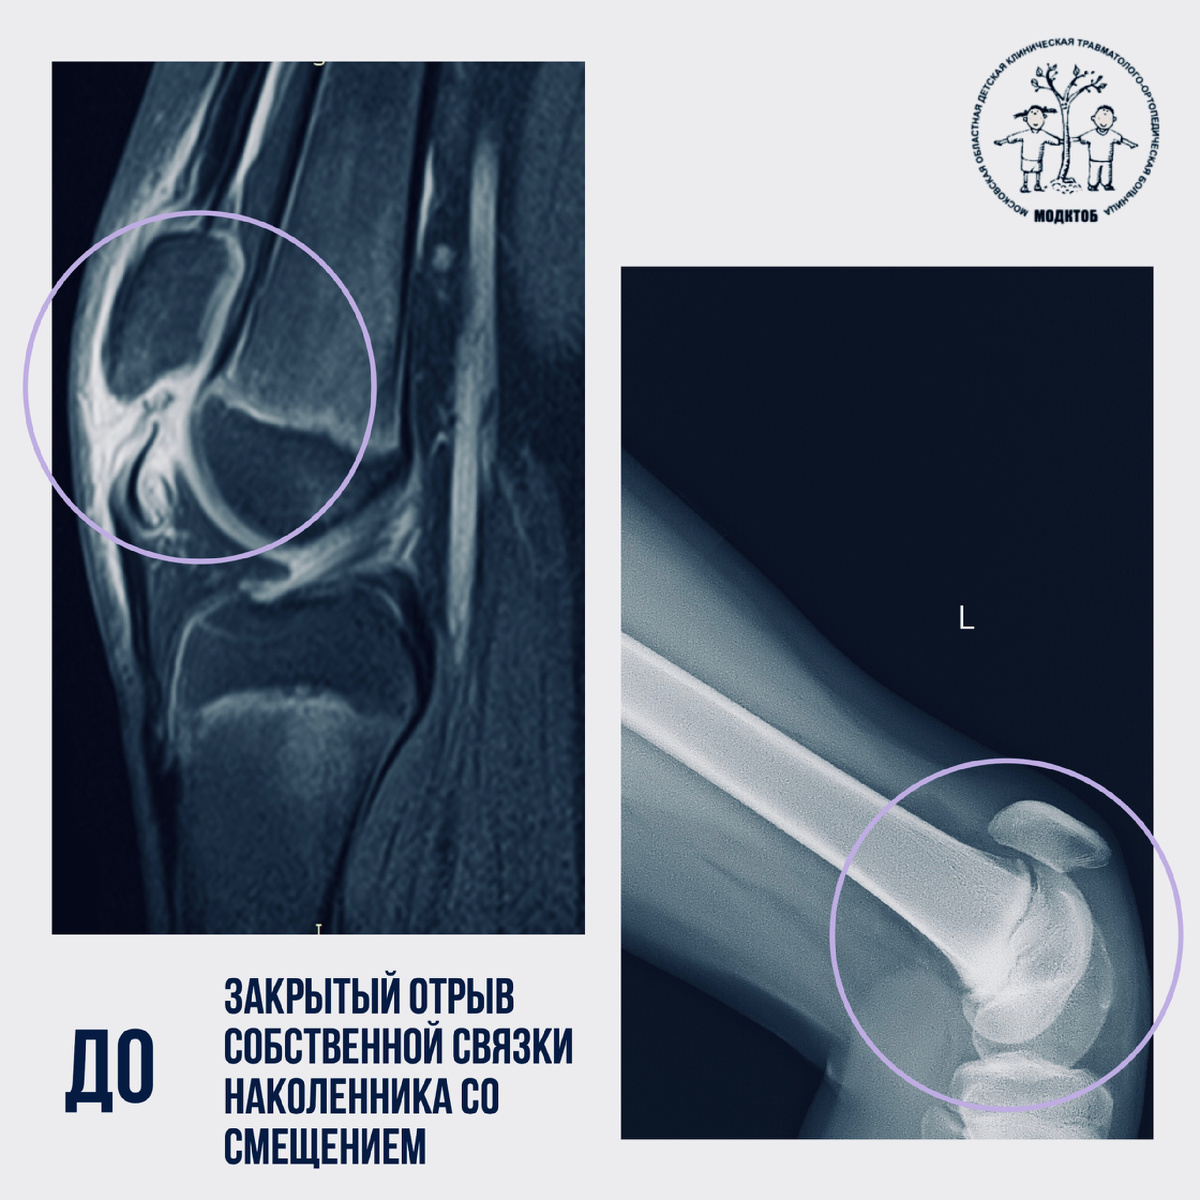

🤾🏼‍♂️ Обычное занятие по волейболу обернулось для подростка серьёзными травмами. Неудачное падение — и сразу два диагноза: закрытый отрыв собственной связки наколенника со смещением и закрытый перелом нижней трети костей предплечья со смещением.

🚑 Бригадой скорой медицинской помощи подросток доставлен в МОДКТОБ, после всех необходимых исследований специалистами принято решение о хирургическом

🚑 Бригадой скорой медицинской помощи подросток доставлен в МОДКТОБ, после всех необходимых исследований специалистами принято решение о хирургическом лечении.

💬 «В ходе одной операции мы выполнили пластику собственной связки надколенника, закрытую репозицию (сопоставление) отломков предплечья и синтез (фиксация) интрамедулярным стержнем лучевой кости», — прокомментировал кандидат медицинских наук, заведующий отделением №3 МОДКТОБ Катин Сергей Владимирович.